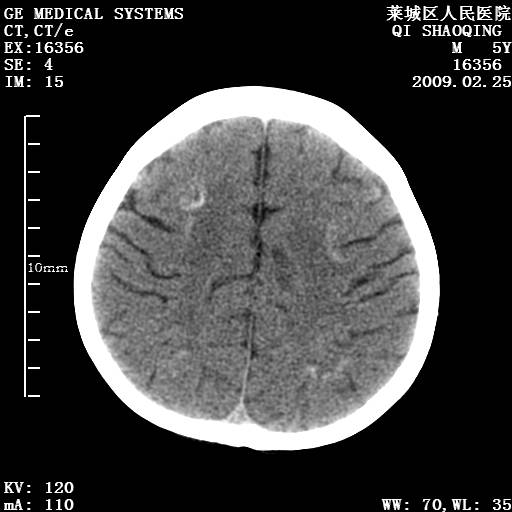

以下是引用wangzhengyuan在2009-2-28 10:22:00的发言:[br]甲状旁腺功能减退引起的脑改变.

以下是引用zsl6918在2009-2-28 10:17:00的发言:[br]首先考虑甲状旁腺功能低下所致,可结合实验室检查明确.另外需除外先天性宫内感染所致.

以下是引用余辉在2009-3-1 9:35:00的发言:[br]患者明显的肢体及智力改变,不支持fahr病,多考虑甲旁低,有可能伴有甲低(呆小症).进一步检查。